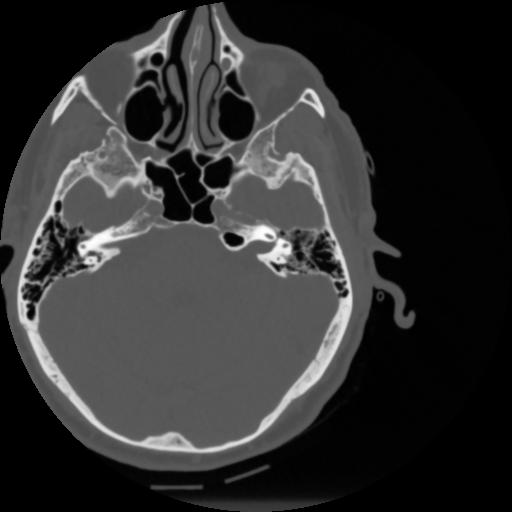

4 CEREBRO,,Vol,0.5,CEREBRO,,